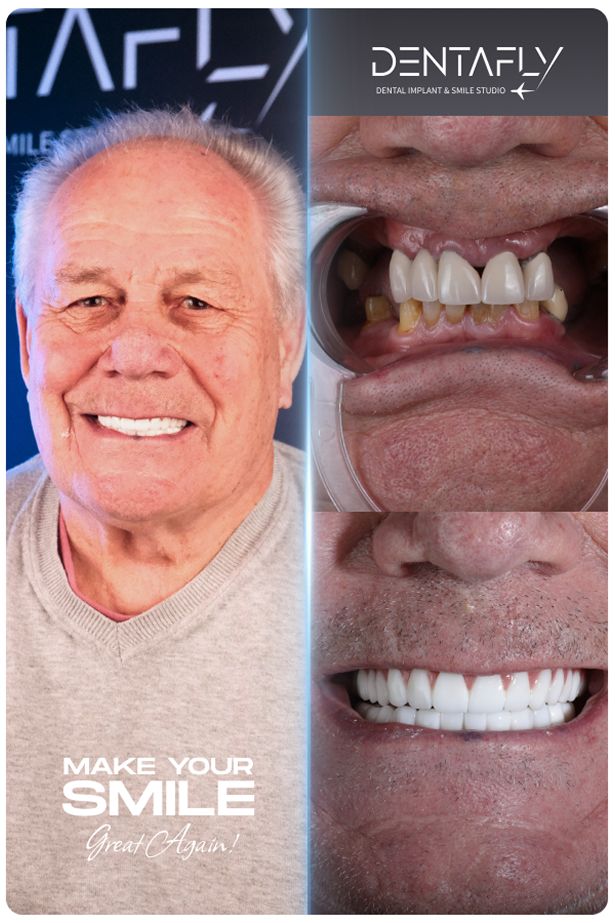

Witness the Transformation: All on 6 Before & After

A permanent full-arch restoration is a masterclass in surgical precision and prosthetic design. Explore our gallery to see how the All on 6 protocol translates into real-world transformations for UK patients—natural finish, restored facial volume, and harmonious smiles.

Witness Digital Precision: The Smile Design Gallery

A flawlessly engineered smile is a masterclass in digital predictability. Explore our exclusive visual gallery to see how advanced 3D planning translates into breathtaking real world transformations for our actual UK patients.